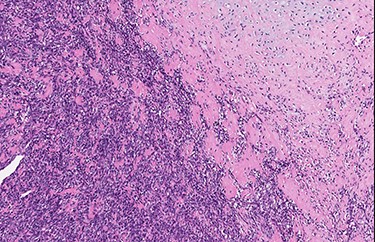

Abrupt transition from small cell component to well differentiated cartilaginous area (H&E, high power view).